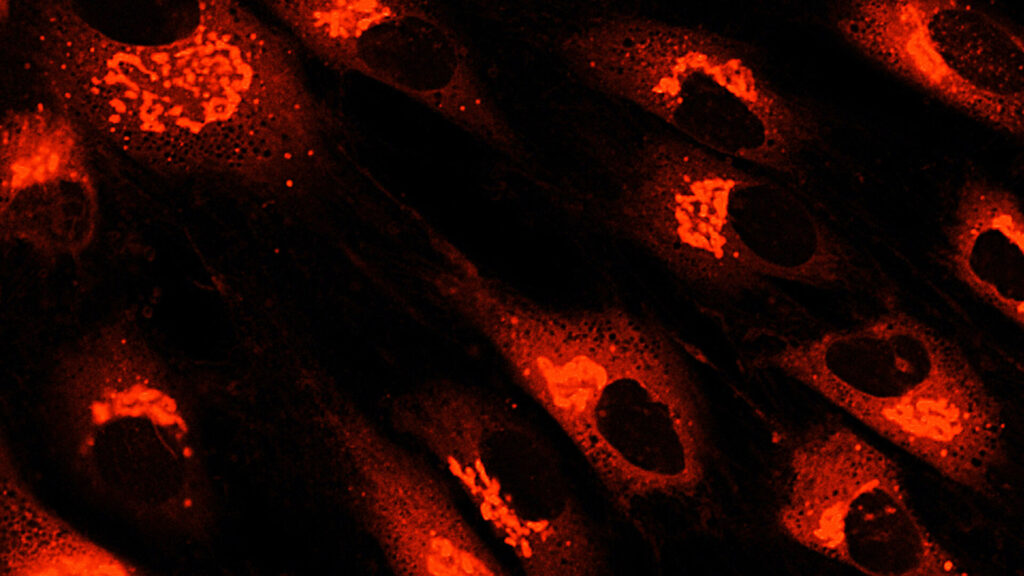

如今,MSC一詞描述了一類細胞,歷史上被稱為間充質干細胞、間充質基質細胞和醫學信號細胞等。間充質干細胞的臨床用途主要歸因于它們的關鍵生物學特性,其中包括:

• 靜脈注射時,它們有可能遷移到組織損傷引起的炎癥部位

• 它們釋放不同生物活性分子的潛力,可以刺激受損細胞的恢復

• 它們預防炎癥和介導抗纖維化作用的能力

• 它們促進免疫調節功能的能力

根據臨床前和臨床證據,間充質干細胞治療免疫和炎癥性疾病顯示出特別的前景,研究人員正在探索間充質干細胞衍生療法和外泌體在治療自身免疫性疾病骨關節炎炎癥性肝病、肺部疾病、移植排斥等方面的臨床應用。人們對同種異體間充質干細胞的興趣也日益濃厚,因為它可以作為現成產品提供。